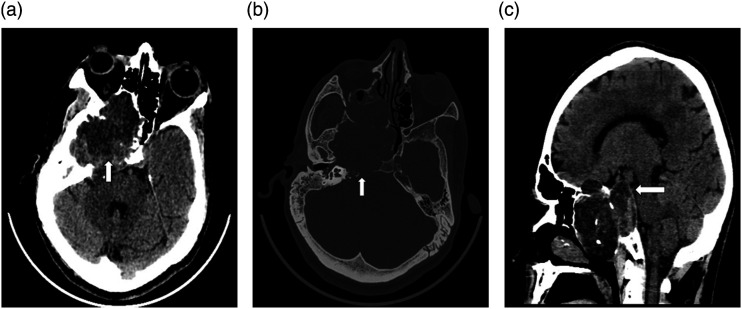

神经节血管瘤是一种罕见的肿瘤,由腹膜后和纵隔后交感神经引起。颅内三叉神经节瘤更为罕见,迄今仅有七例报道。我们报告了一例 65 岁男性的病例,他患有右侧搏动性头痛,右眼失明。磁共振成像显示,中颅窝有一个界限不清的肿块病变,少数区域的表观弥散系数降低,并有多处微出血。通过翼下和颞下入路进行右侧中开颅手术,对肿瘤进行了碎块剥离。检测到的组织学特征与三叉神经节瘤(成熟型)相符。

Ganglioneuromas are rare tumors arising from retroperitoneal and posterior mediastinal sympathetic nerves. Intracranial trigeminal nerve ganglioneuromas are even more rare, with only seven cases reported to date. We present a case of a 65-year-old male with a right-sided throbbing headache type and blindness in his right eye. Magnetic resonance imaging revealed an ill-defined mass lesion in the middle-cranial fossa, with a few areas having a reduced apparent diffusion coefficient and multiple microhemorrhages. Piecemeal debulking of the tumor was achieved by performing a right-middle craniotomy via the pterionic and sub-temporal approach. The detected histological features matched those of a ganglioneuroma (maturing type) of the trigeminal nerve.